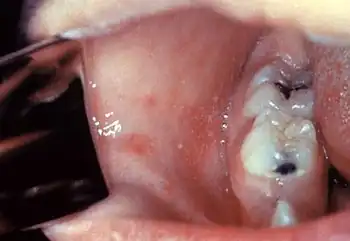

Koplik's spots seen inside the mouth are diagnostic for measles, but are temporary and therefore rarely seen.[24] Koplik spots are small white spots that are commonly seen on the inside of the cheeks opposite the molars.[23] They appear as "grains of salt on a reddish background."[26] Recognizing these spots before a person reaches their maximum infectiousness can help reduce the spread of the disease.[27]